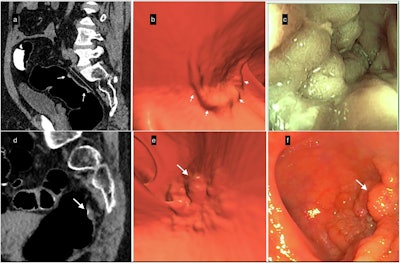

Lateral spreading tumors (LSTs). (a–c) Example of LST-non-granular (LST-NG). (a) Sagittal 2D-image with 40–400-HU abdominal window setting indicates a large 5.6-cm lesion with subtle diffuse thickening of the rectal wall (white arrows); the surface is partially covered by a thin layer of orally administered contrast agent. (b) The appearance of the villous mat on the 3D endoscopic view highlights the nodular aspect (white arrows) at the periphery of the lesion. (c) The optical colonoscopy view with the final diagnosis of a carpet villous adenoma with low-grade dysplasia. (d–f) Example of an LST-granular (LST-G) lesion. (d) Sagittal 2D image indicating nodular thickening of the rectum wall with a 10-mm nodule (white arrow). (e) The 3D endoscopic view visualized the irregular LST with a large nodule (white arrow), similar to (f) the endoscopic image obtained the same day after CTC. It confirmed the diagnosis and allowed mucosectomy with a final pathology report of a tubulous lesion with high-grade dysplasia.All images courtesy of Dr. Mehdi Cadi et al and Insights into Imaging